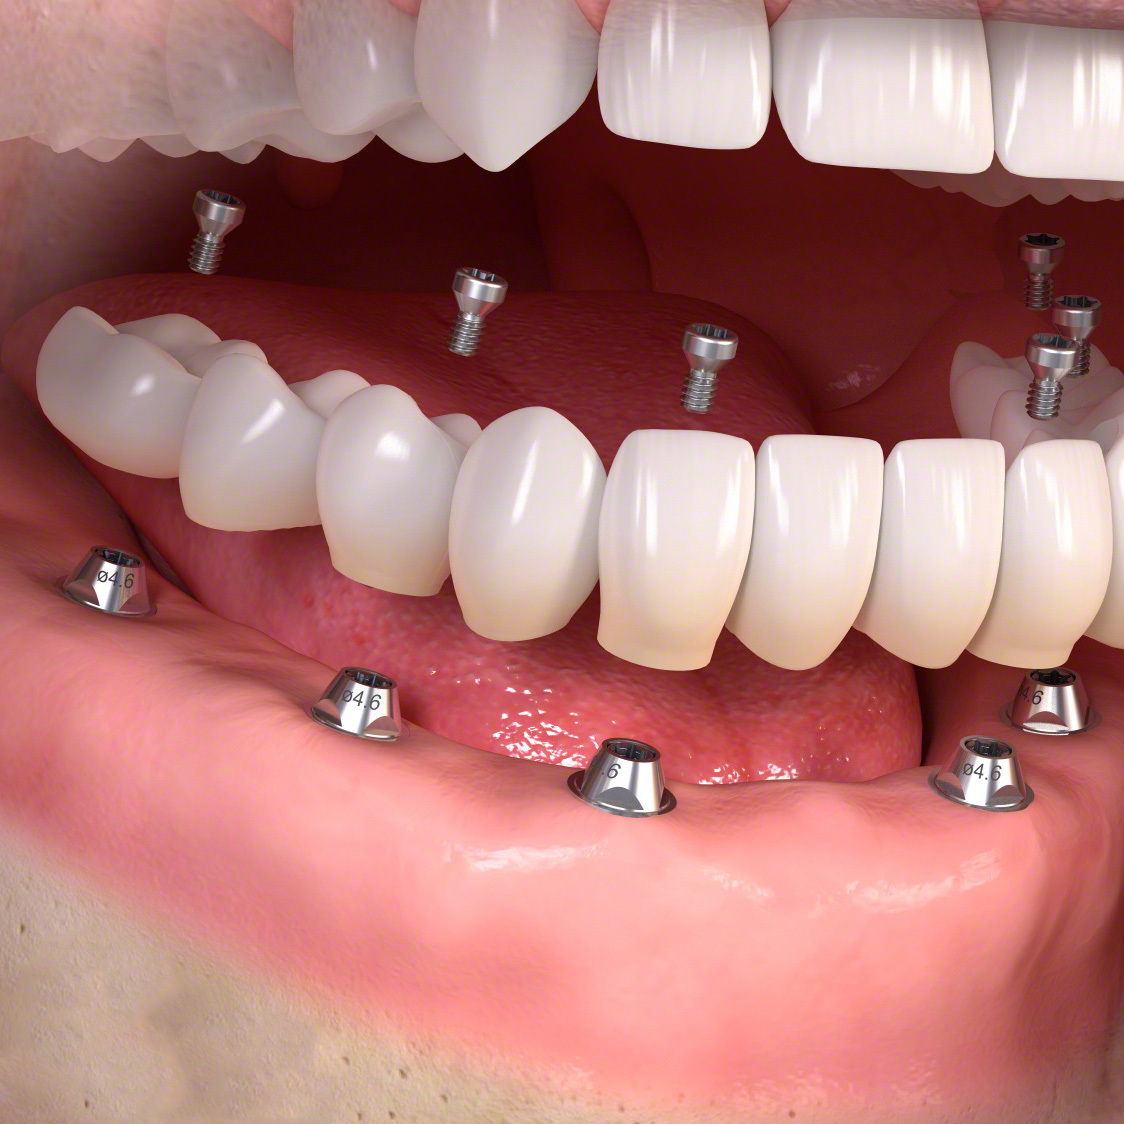

多くの歯を失ったケース

固定式タイプ

・5~8本のインプラントによって自分の歯のように噛めるよう修復

多くの歯を失った場合。

手術でインプラントを埋める。

人工歯を装着します。

インプラント治療で修復。

歯周病とインプラント(抜歯即時荷重)<ガイドシステムを使用した埋入法>

インプラント8本で14本の歯を並べたケース・仮歯代含む (函南町在住 女性

抜歯後、片顎8本のインプラントを埋入し、即日に仮歯を製作する事により、1日で片顎14本の歯を回復します。事前にインプラントを埋入する位置をCTによりシミュレーションし、埋入ガイド、仮歯を準備したうえで手術を行います。埋入ガイドにより、正確な位置にインプラントを埋入することができます。